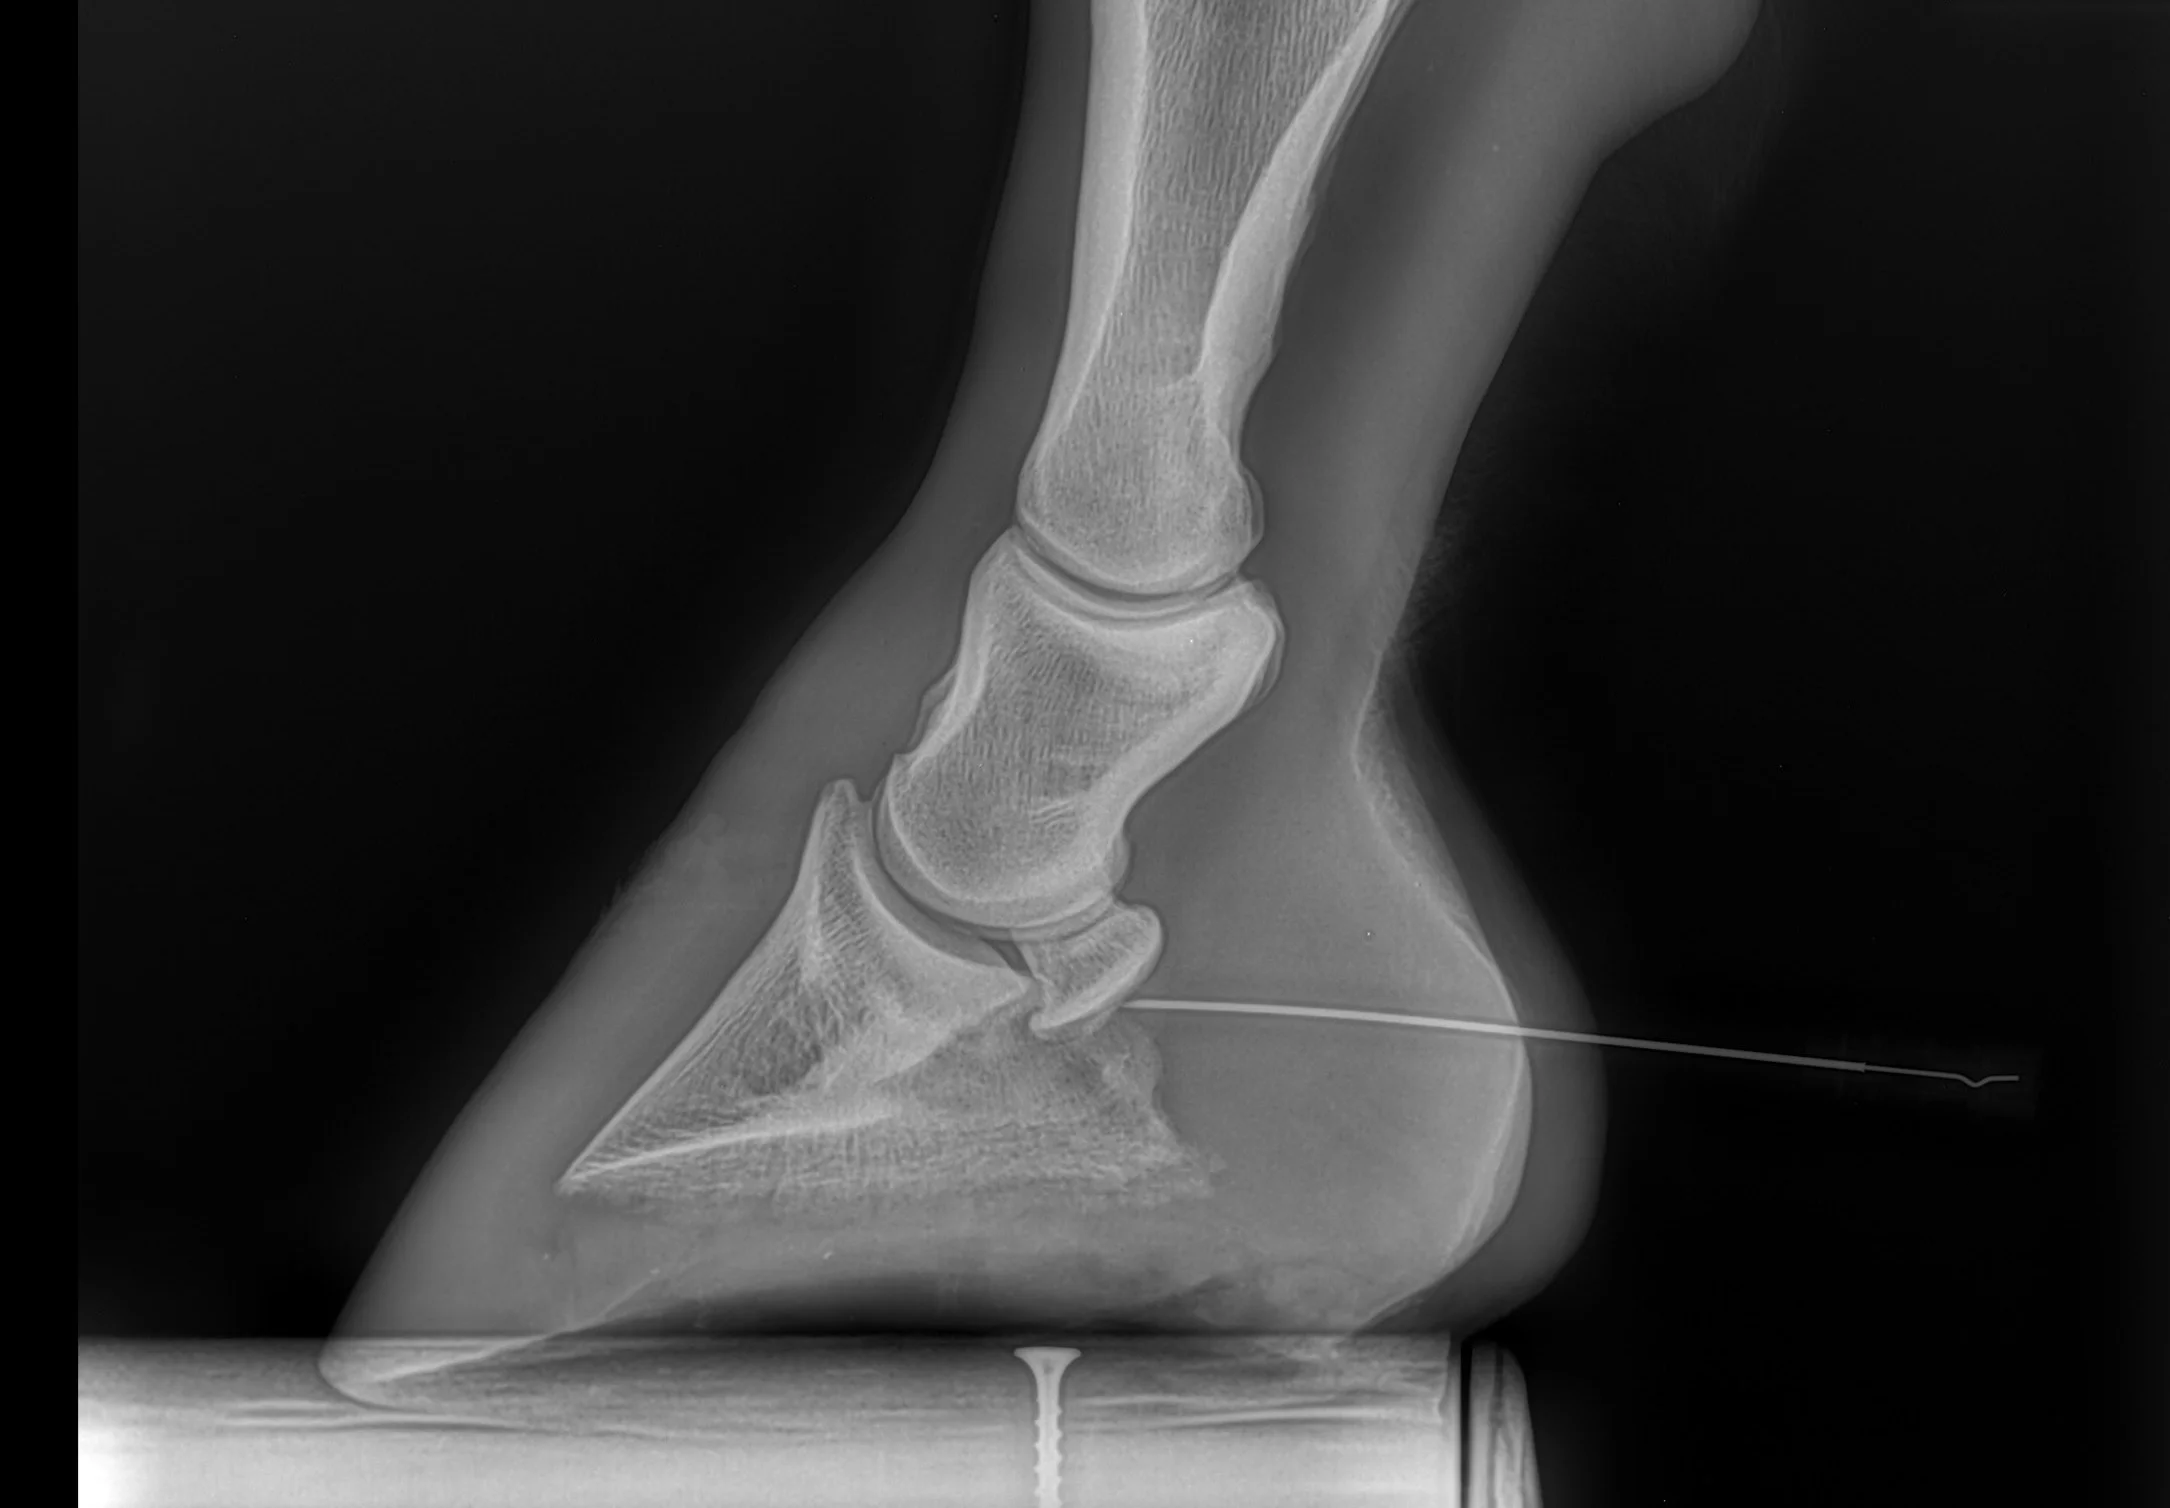

From innovativeequinepodiatry.blogspot.com

Innovative Equine Podiatry New navicular case study Equine Navicular Bursa Injections Learn how veterinarians treat navicular syndrome in horses with a coffin joint injection of triamcinolone acetonide (ta). Injection of the navicular bursa is commonly performed from the palmar aspect of the limb, which results in penetration of the deep digital flexor tendon (ddft). Needle placement for treatment of the navicular. A novel technique for injecting the equine navicular bursa using. Equine Navicular Bursa Injections.